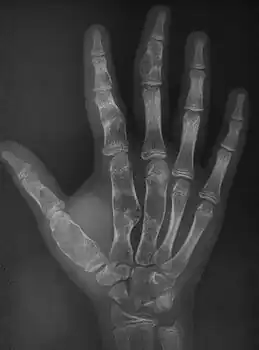

X-ray wrist: Ollier disease in child -

X-ray hand:Ollier disease in child